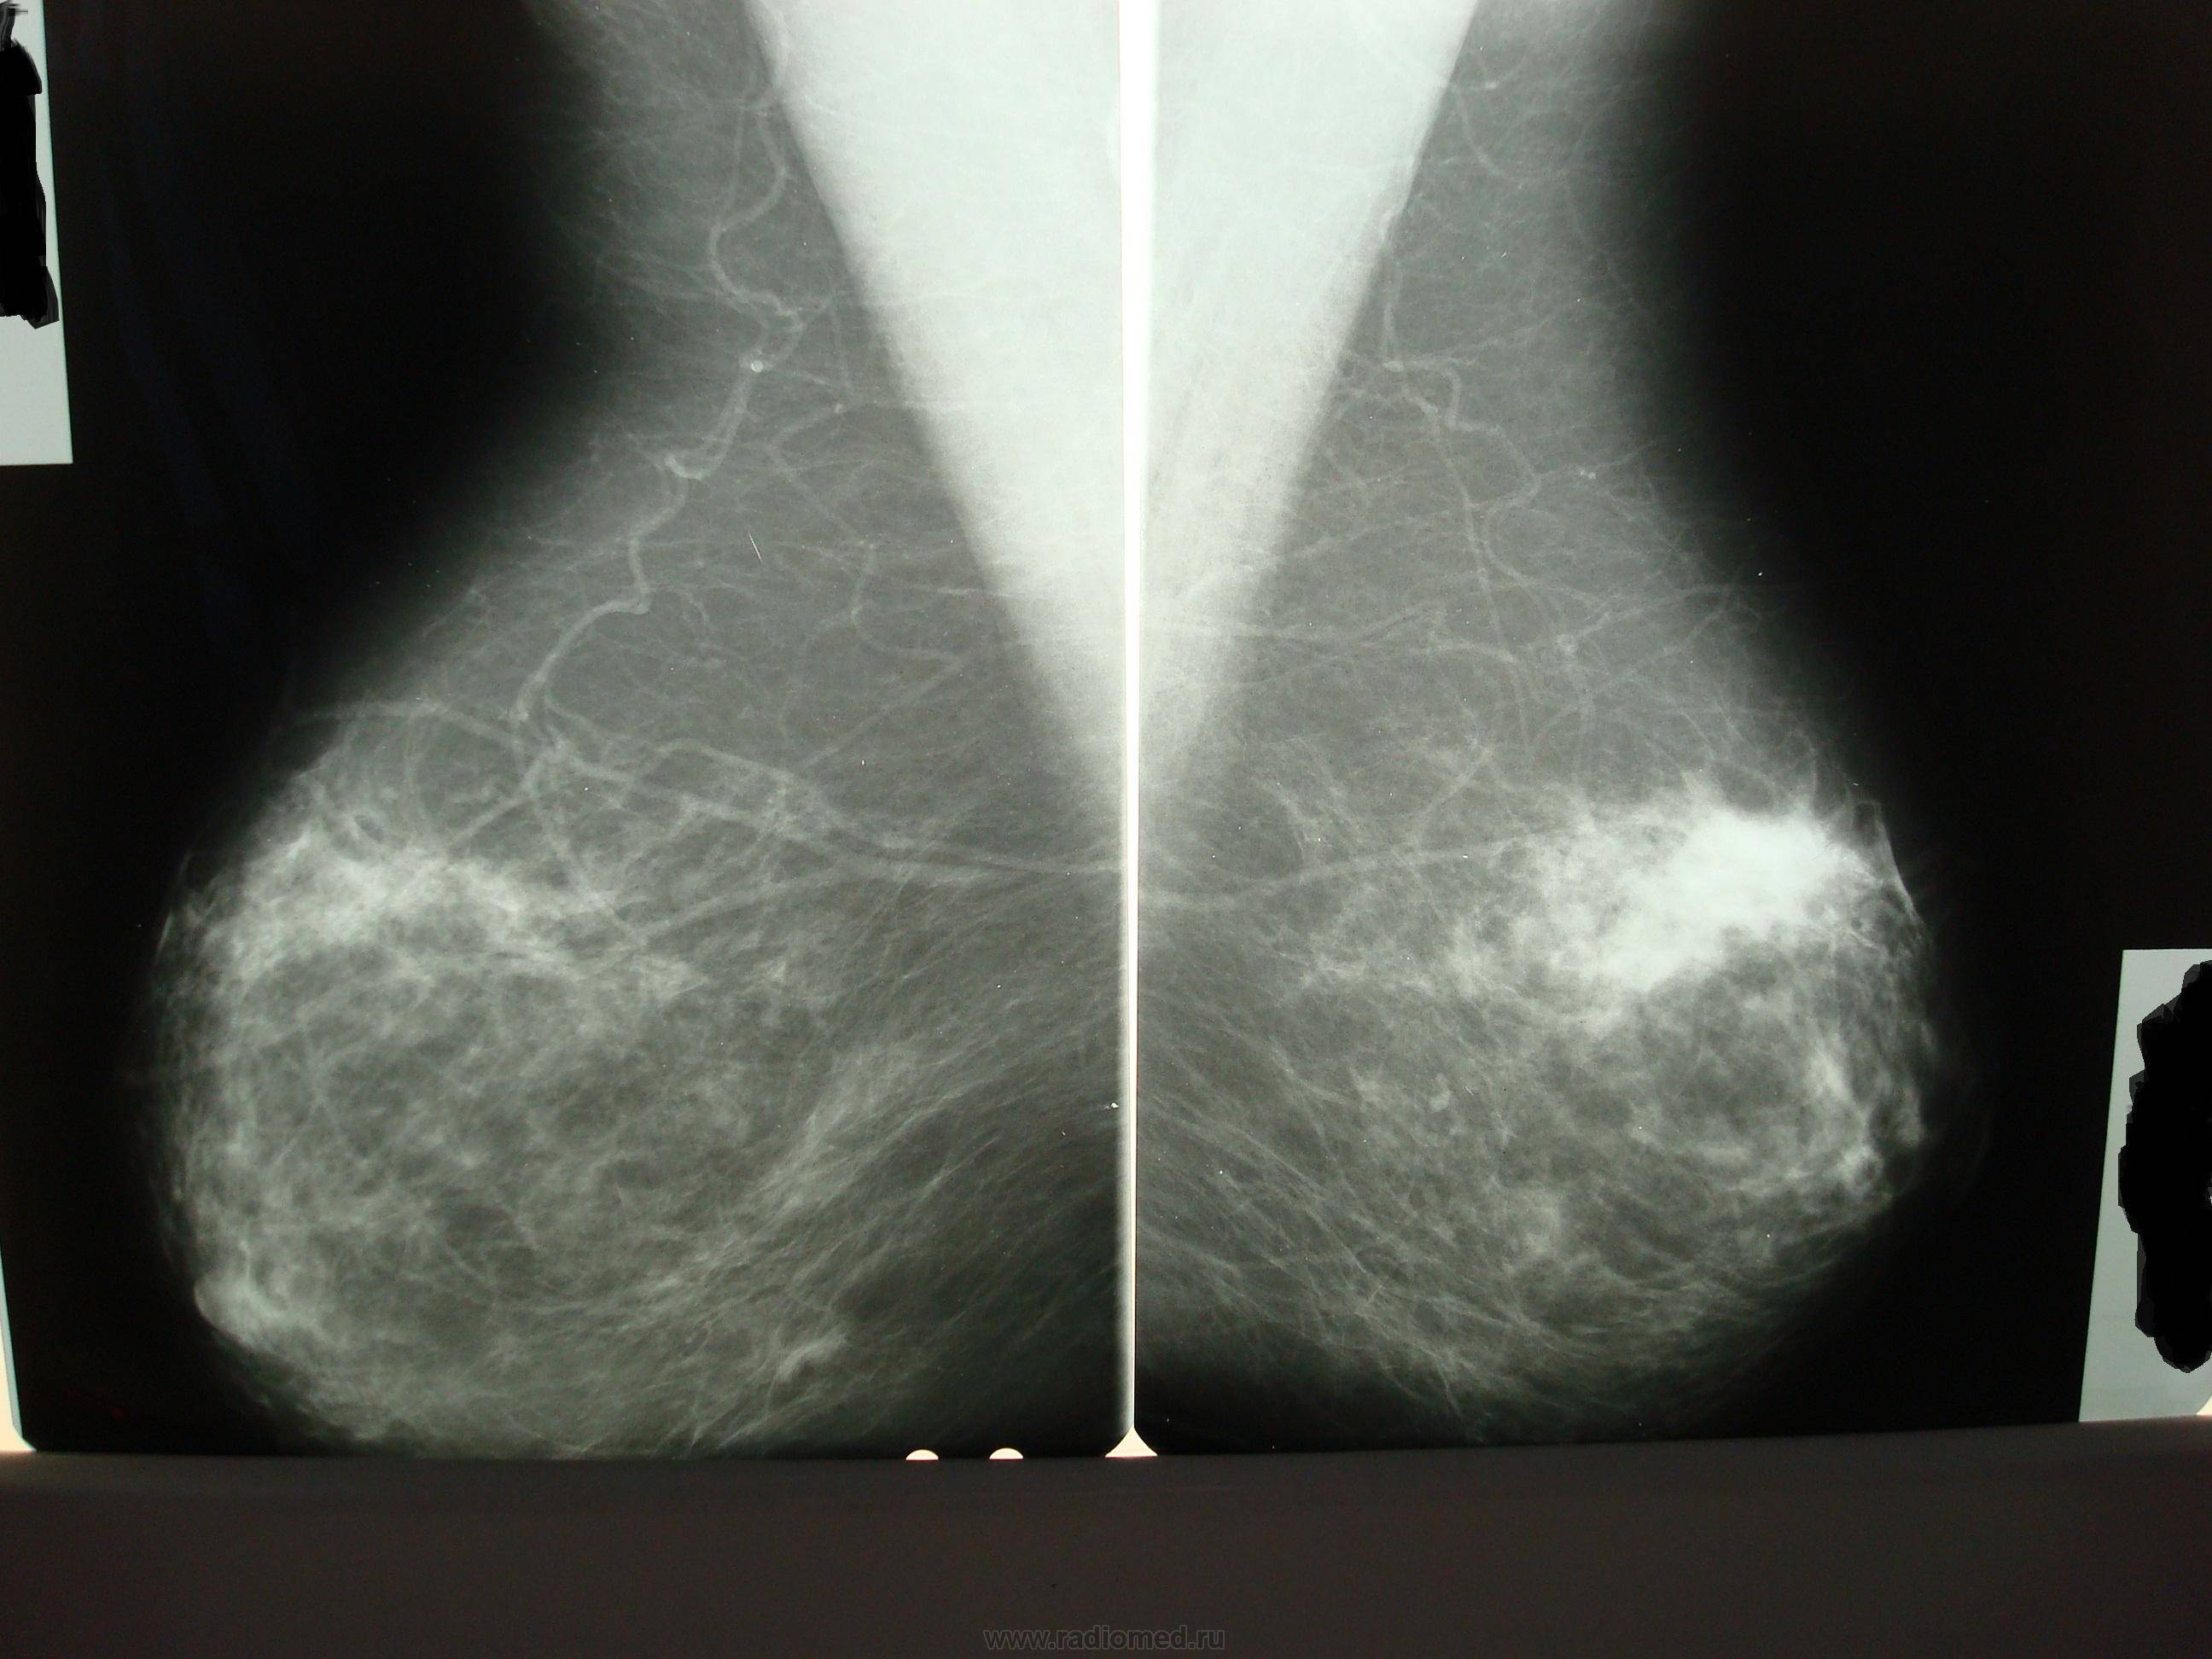

Что такое маммография: важность, процесс и результаты